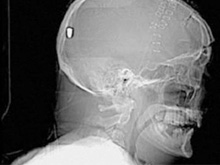

В Британии врачи нашли у пациента пулю в голове13.05.10 13:07 Прочтений новости 1078 Общество В Британии у пациента, который поступил в клинику с подозрением на инсульт, врачи обнаружили пулю в голове. Но остается неизвестным, как мужчина получил ранение.Рентгеновские снимки головы показали, что в полости черепа находится инородный предмет. Мужчине сделали томографию головы, и врачи установили, что этим предметом является пуля. Как сообщается, 19 апреля 61-летний Питер Хесфорд упал во время работы у себя в саду. Позже его обнаружила жена, которая вызвала скорую. Мужчина оставался в сознании, но не мог говорить. Медики, прибывшие на место, заподозрили у Питера Хесфорда инсульт и доставили его в Больницу Уитеншо. Эксперты по баллистике, изучив снимки пациента, пришли к выводу, что пуля, застрявшая в затылочной области, могла попасть туда через глаз. Но мужчина не помнит, что именно с ним произошло. Врачи попытались удалить пулю, однако это оказалось невозможным из-за ее положения по отношению к окружающим структурам. Пациент остается в больнице, а его состояние расценивается как стабильное. Комментарии (всего 0)